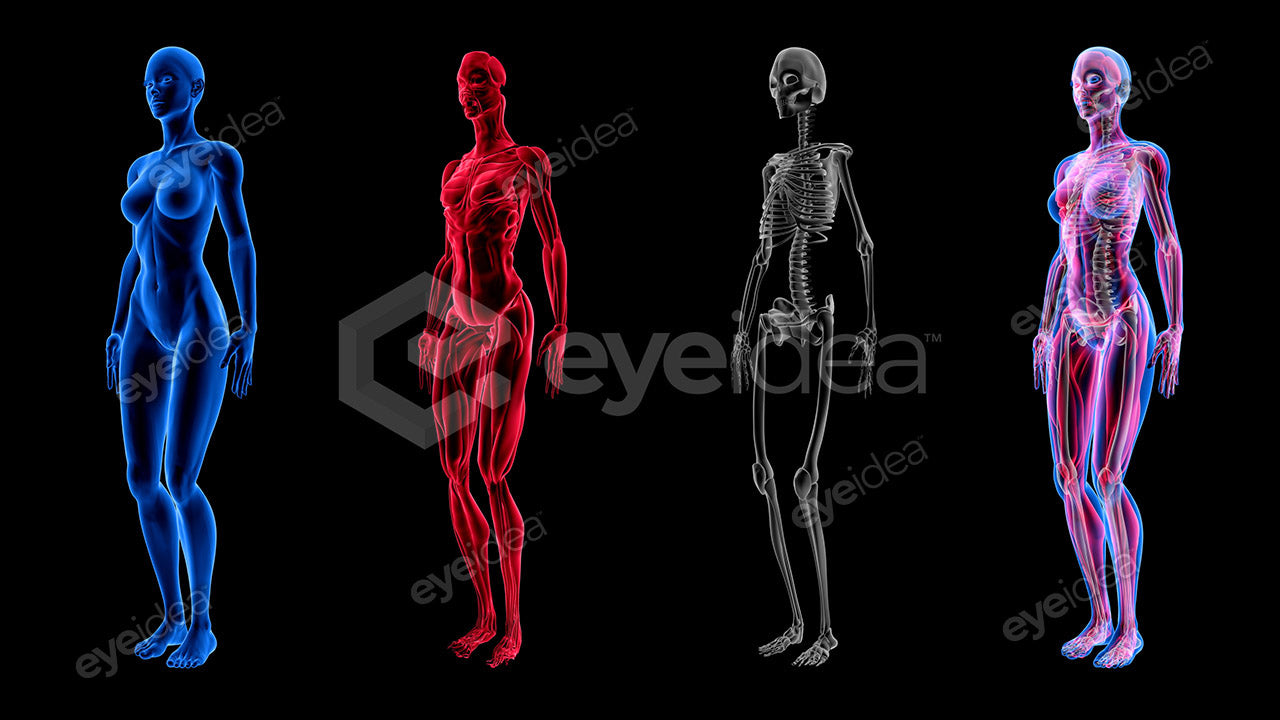

Versatility and Variety

Our Stock-Packs™ are curated to include a varied

range of angles, motion, styles and formats,

ensuring that creators can find the assets

they want fast and easy.